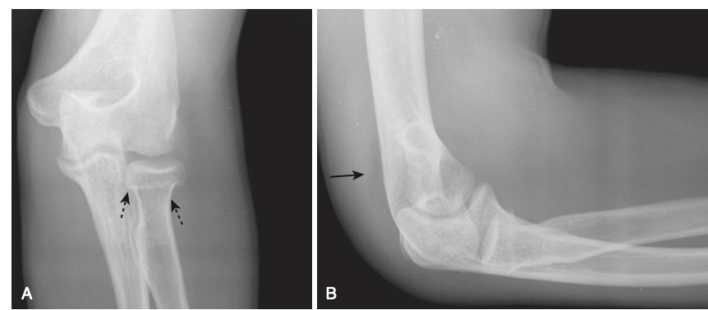

Gãy đài quay (chỏm xương quay, radial head fracture)

- Là gãy xương thường gặp nhất của khuỷu tay ở người lớn.

- Tìm kiếm dấu tăng sáng hình liềm của mỡ dọc bờ sau của đầu dưới xương cánh tay do lớp mỡ ngoài bao hoạt dịch, trong bao khớp (bình thường không nhìn thấy được) bị đẩy khỏi xương do máu tụ sau chấn thương – dấu hiệu đệm mỡ phía sau dương tính (Hình 16).

- Một dấu hiệu nữa là đường quay chỏm con, được vẽ qua trung tâm của cổ xương quay sẽ đi qua trung tâm của chỏm con xương cánh tay bất kể tư thế của người bệnh, vì bản lề của xương quay và chỏm con là cố định. Trong trật khớp, gãy chỏm xương quay, đường này sẽ không đi qua trung tâm của chỏm con (hình 17).